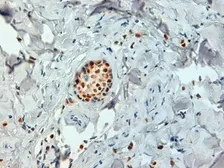

Description Mouse MonoclonalApplications WB ICC/IF IHC-P IHC-Fr FCM Dot ChIP assay IHC-P (cell pellet)Reactivity Hu, Ms, MkSummary Strong Erb staining in epithelial cell nuclei. Occasional weak to moderate staining is seen in surrounding stromal and endothelial cell nuclei. Sporadic light cytoplasmic staining is sometimes observed. We have also successfully detected ERb in colon and ovarian tumors using the same antibody.